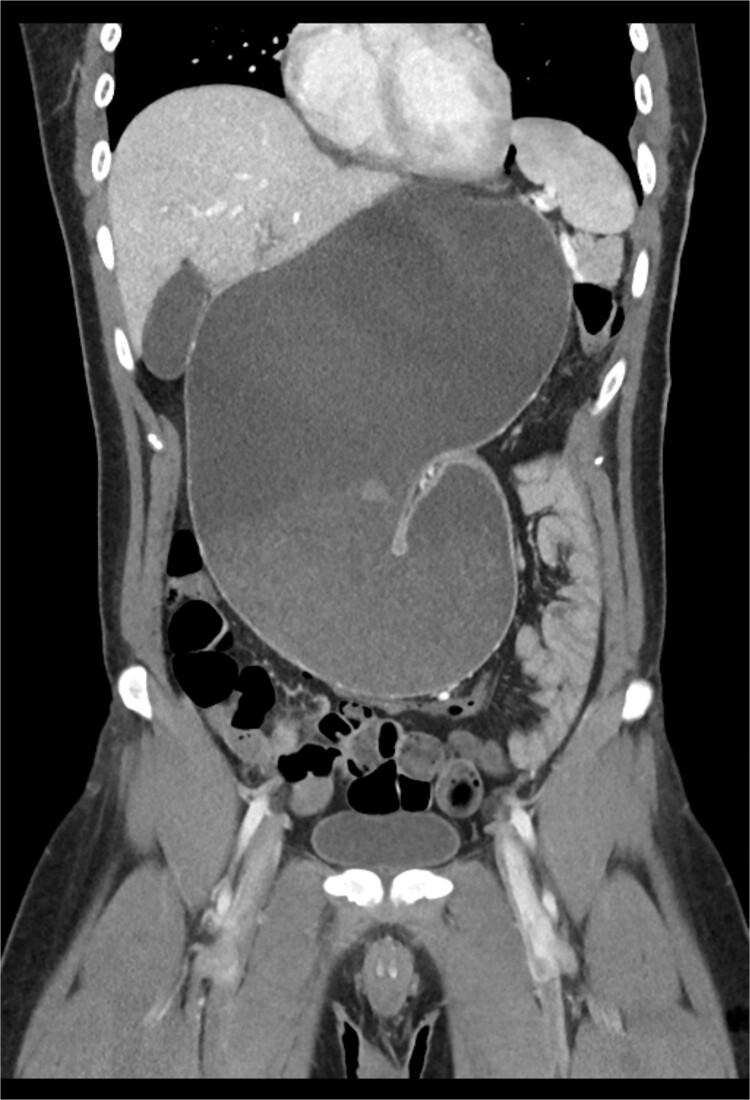

Gastric volvulus has been rarely associated with diaphragmatic paralysis or eventration. In this article, we present the case of a patient with idiopathic paralysis of the left hemidiaphragm that underwent treatment with a robotic thoracoscopic diaphragm plication, which was complicated by massive gastric volvulus resulting in such significant intra-abdominal hypertension that the ipsilateral diaphragm ruptured anterior to the plication suture line.

胃扭转很少与膈麻痹或膈膨出相关。在本文中,我们报告了一例特发性左半膈麻痹患者,该患者接受了机器人胸腔镜膈折叠术治疗,术后并发大量胃扭转,导致严重的腹腔内高压,使得同侧膈肌在折叠缝线前方破裂。